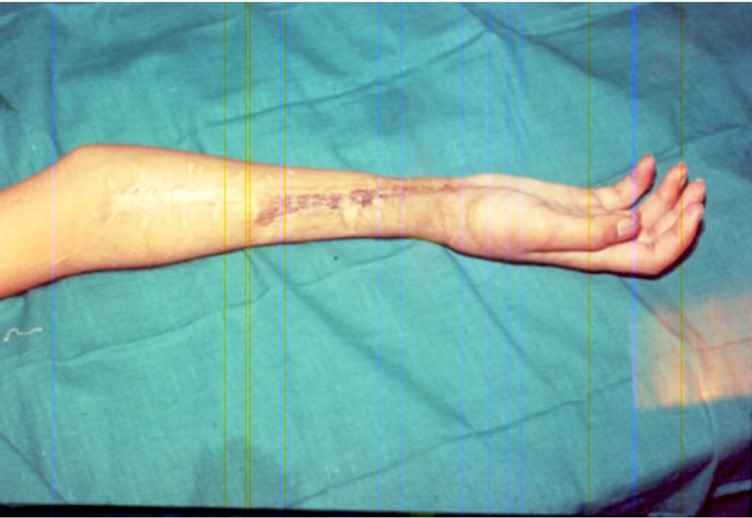

With time, the wounds had healed but with a scarred forearm. He had very stiff fingers, with no movements. There were ununited forearm bones. There was no sensation in the fingers either. He and the entire family seemed to have lost everything in life as he was issued with a 100% disability certificate. In other words, the certificate stated that there was no hope that he could use his right hand again, as before.

The next problem was related to the skin. The skin from the tummy or the abdominal area was transferred to the forearm. This also went on smoothly and so the third target of skin loss had been achieved successfully. So now the two problems were restoration of finger flexion and the sensation because of the nerve loss.